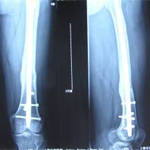

張某,男,50歲,因“左股骨骨不連”入院。植骨+PRP治療后8月完全愈合。

術后完全愈合